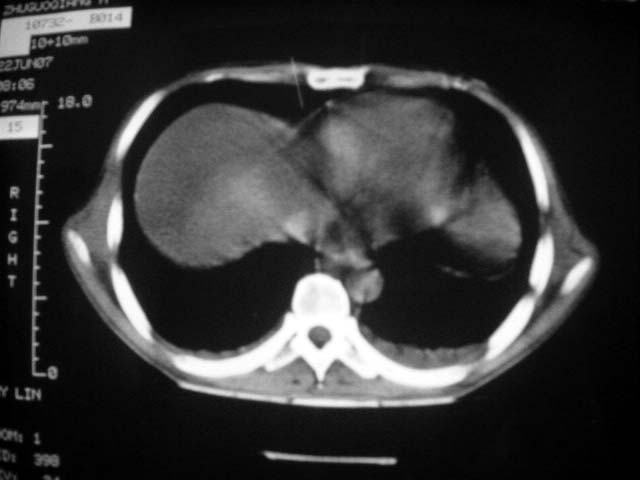

前几次大家认为是转移癌,但此次复查病灶却明显吸收好转,不支持诊断。请大家讨论。[emb10]

双侧继发性肺结核伴两肺播散灶.双侧胸腔少量积液

双肺感染, 双侧胸腔少量积液

根据前后片比较应该考虑迁徙性肺脓肿,回帖相差甚远是因为前后片变化太大出乎大家意料之外,这就是影象诊断要结合临床复查对比的必要性,

回顾既往片,病变明显吸收,缩小,未经治疗,不支持肺转移瘤,可能为肺结节病或韦格氏肉芽肿

患者近期复查胸ct正常,轻度肝功异常,保肝、抗病毒(拉美夫叮)治疗中。